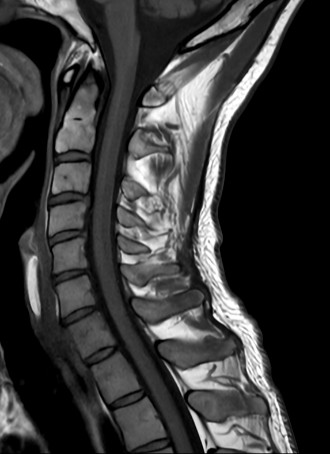

High quality Cervical Spine imaging with SmartSpeed Precise